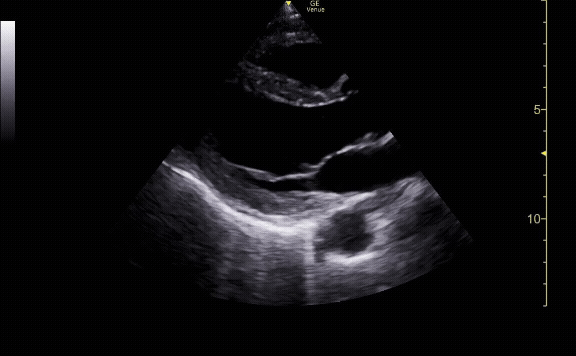

View of the IVC and hepatic vein leading to the right atrium

c/o Victoria Gonzalez, MD